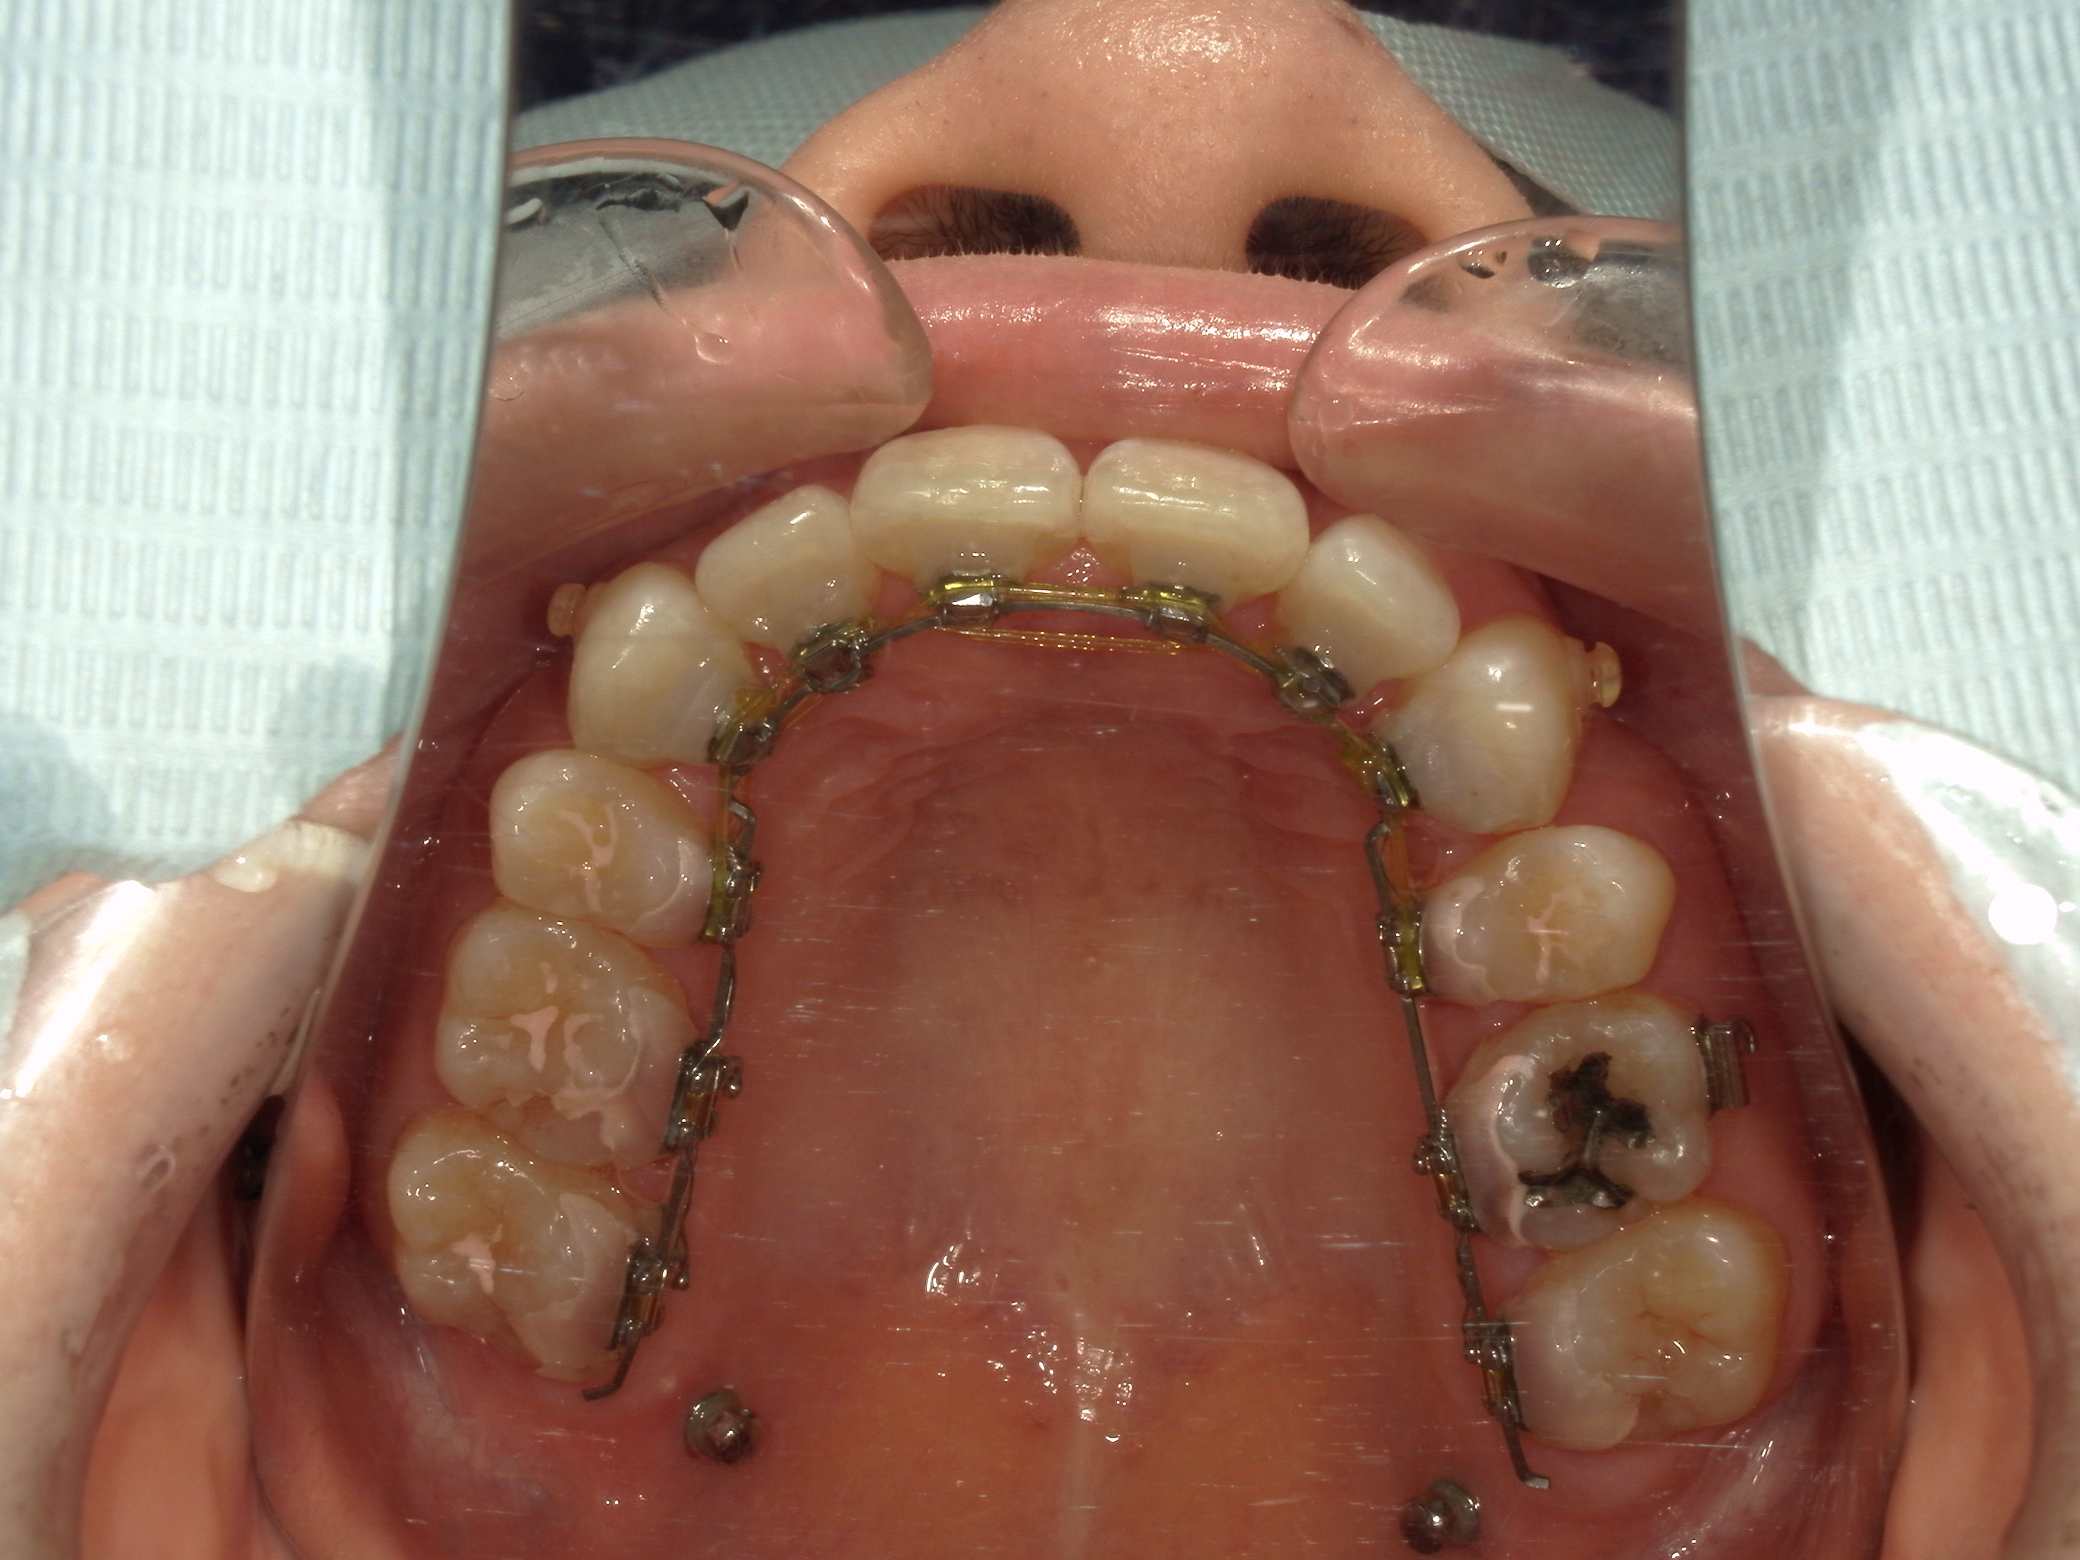

本症例は上下小臼歯抜歯により叢生解消のスペースを獲得し、下顎位の後退があることからダイレクトスプリント治療を併用して顎位の安定を求めた。

矯正用アンカースクリューは固定源の強化のために必要とした。